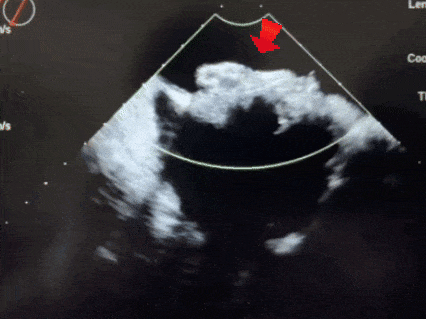

超声下,封堵器左右盘面贴合房间隔两侧

锁定后,超声下观察封堵器结构,盘面呈标准的三明治结构,成型良好

释放后超声

释放封堵器后,封堵器盘面稳固贴壁,成型良好,超声下未见分流,封堵成功。

四腔心切面下观察封堵器,左右盘面稳固贴壁,盘面平整,未影响瓣膜结构

主动脉短轴切面下观察封堵器,封堵器形态稳定,无残余分流